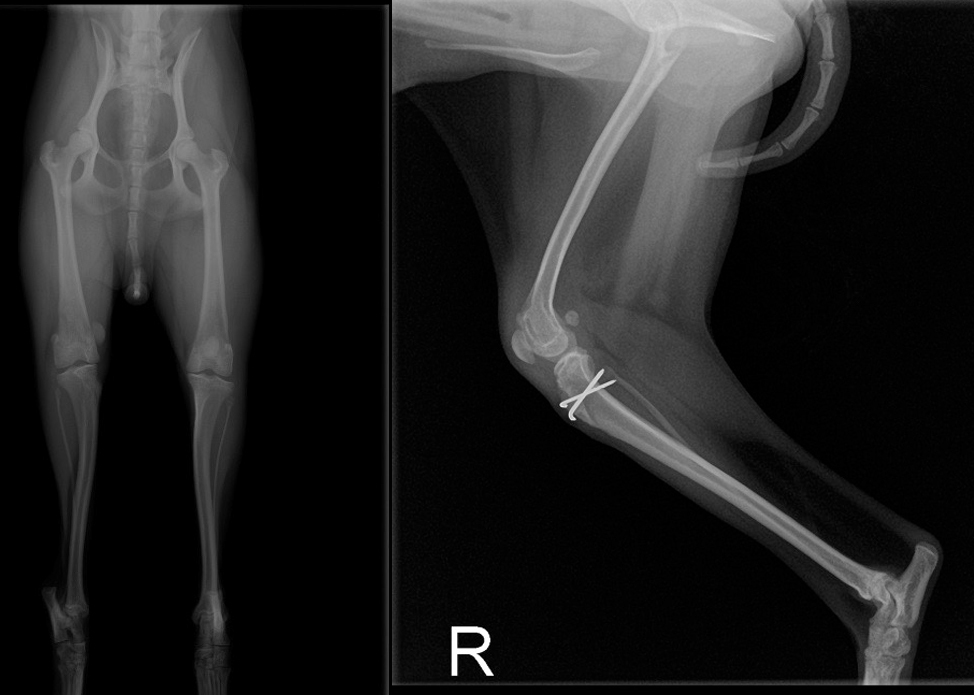

整形外科

まずは、「丁寧に触ること = 触診」 をして、痛みの部位を特定していきます。

レントゲン検査はしっかりと撮影します。

検査に麻酔は必要ありません。動物に負担のない検査です。

手術が本当に必要かどうか、どの手術方法が良いのか様々なご提案をさせていただきます。